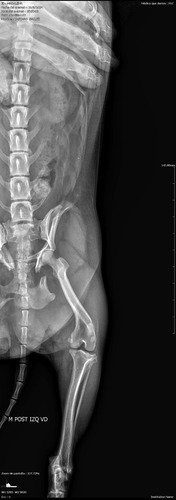

No dia 18/05 ela foi brutalmente atropelada, e teve parte da sua pélvis destruída. São muitas fraturas nos ossos do quadril, lesões na bexiga, compressão do intestino e muitos cortes no corpo todo.

Felizmente ela está estável e o seu quadro é reversível mediante cirurgia de reconstrução dos ossos. A cirurgia é bem complexa e delicada, devido ao porte da Madalena (pesa apenas 4 kilos)

Já realizou exames de ultrassonografia do abdômen, radiografias, exames de sangue, eletrocardiograma e o pré cirúrgico.